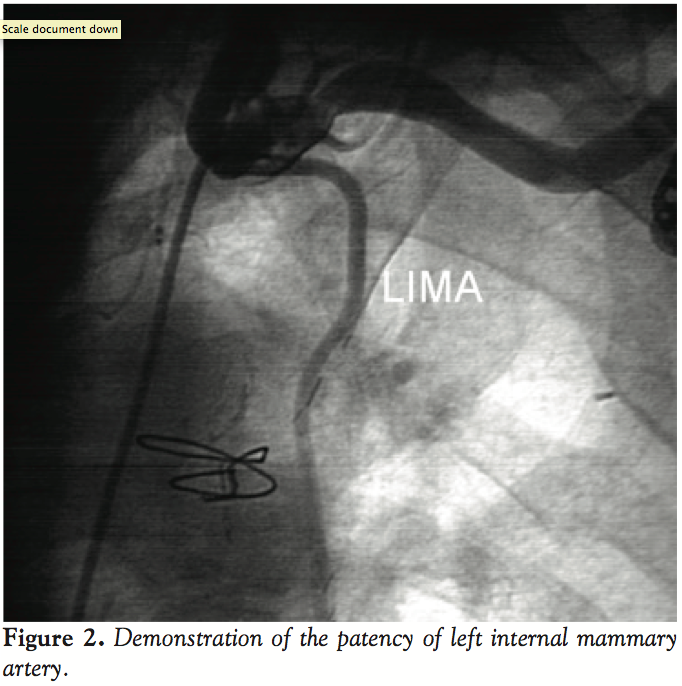

However, many attempts to visualize the bypass grafting of the left internal mammary artery (LIMA) to the LAD failed as the left subclavian artery could not be engaged at aortic arch. After an aortography, we found that the ostium took its origin 5 cm below its presumed position (Figure 1). Thereafter, the left subclavian artery was successfully engaged with a Judkins right 4 catheter and the LIMA was selectively cannulated to check distal patency (Figure 2). Percutaneous interventions for significant occlusions in the left circumflex and right coronary arteries were successfully performed without any complication. No other congenital anomaly was detected in the patient. He was discharged uneventfully on post-admission day 4.